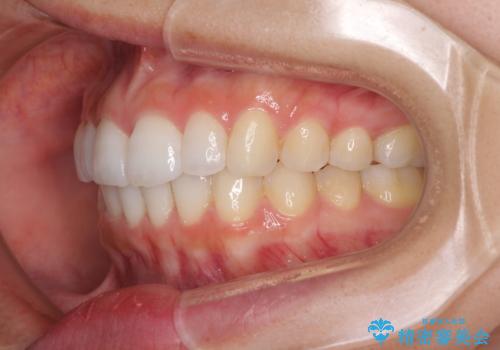

口が閉じにくい 1本飛び出した前歯の矯正治療

- 1本飛び出した前歯を治したいとのことで来院された患者様です。

歯列全体の拡大とIPR(歯と歯の間を削る)によってデコボコが解消するようにし、さらにゴムかけを活用して右側の咬み合わせ位置を変えるように設計し、インビザラインにより治療を行うこととしました。

結婚式までに前歯を整えたいとのことでしたが、インビザラインでは先に奥歯を移動させてから前歯を動かすため、間に合わない可能性がありました。しかし、結婚式までに期間があったことと、マウスピースをしっかりと装着してくださったことで、十分な歯列に整えることができました。